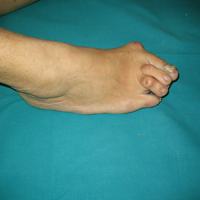

• Κότσια - Εξαρθρήματα μεταταρσίων